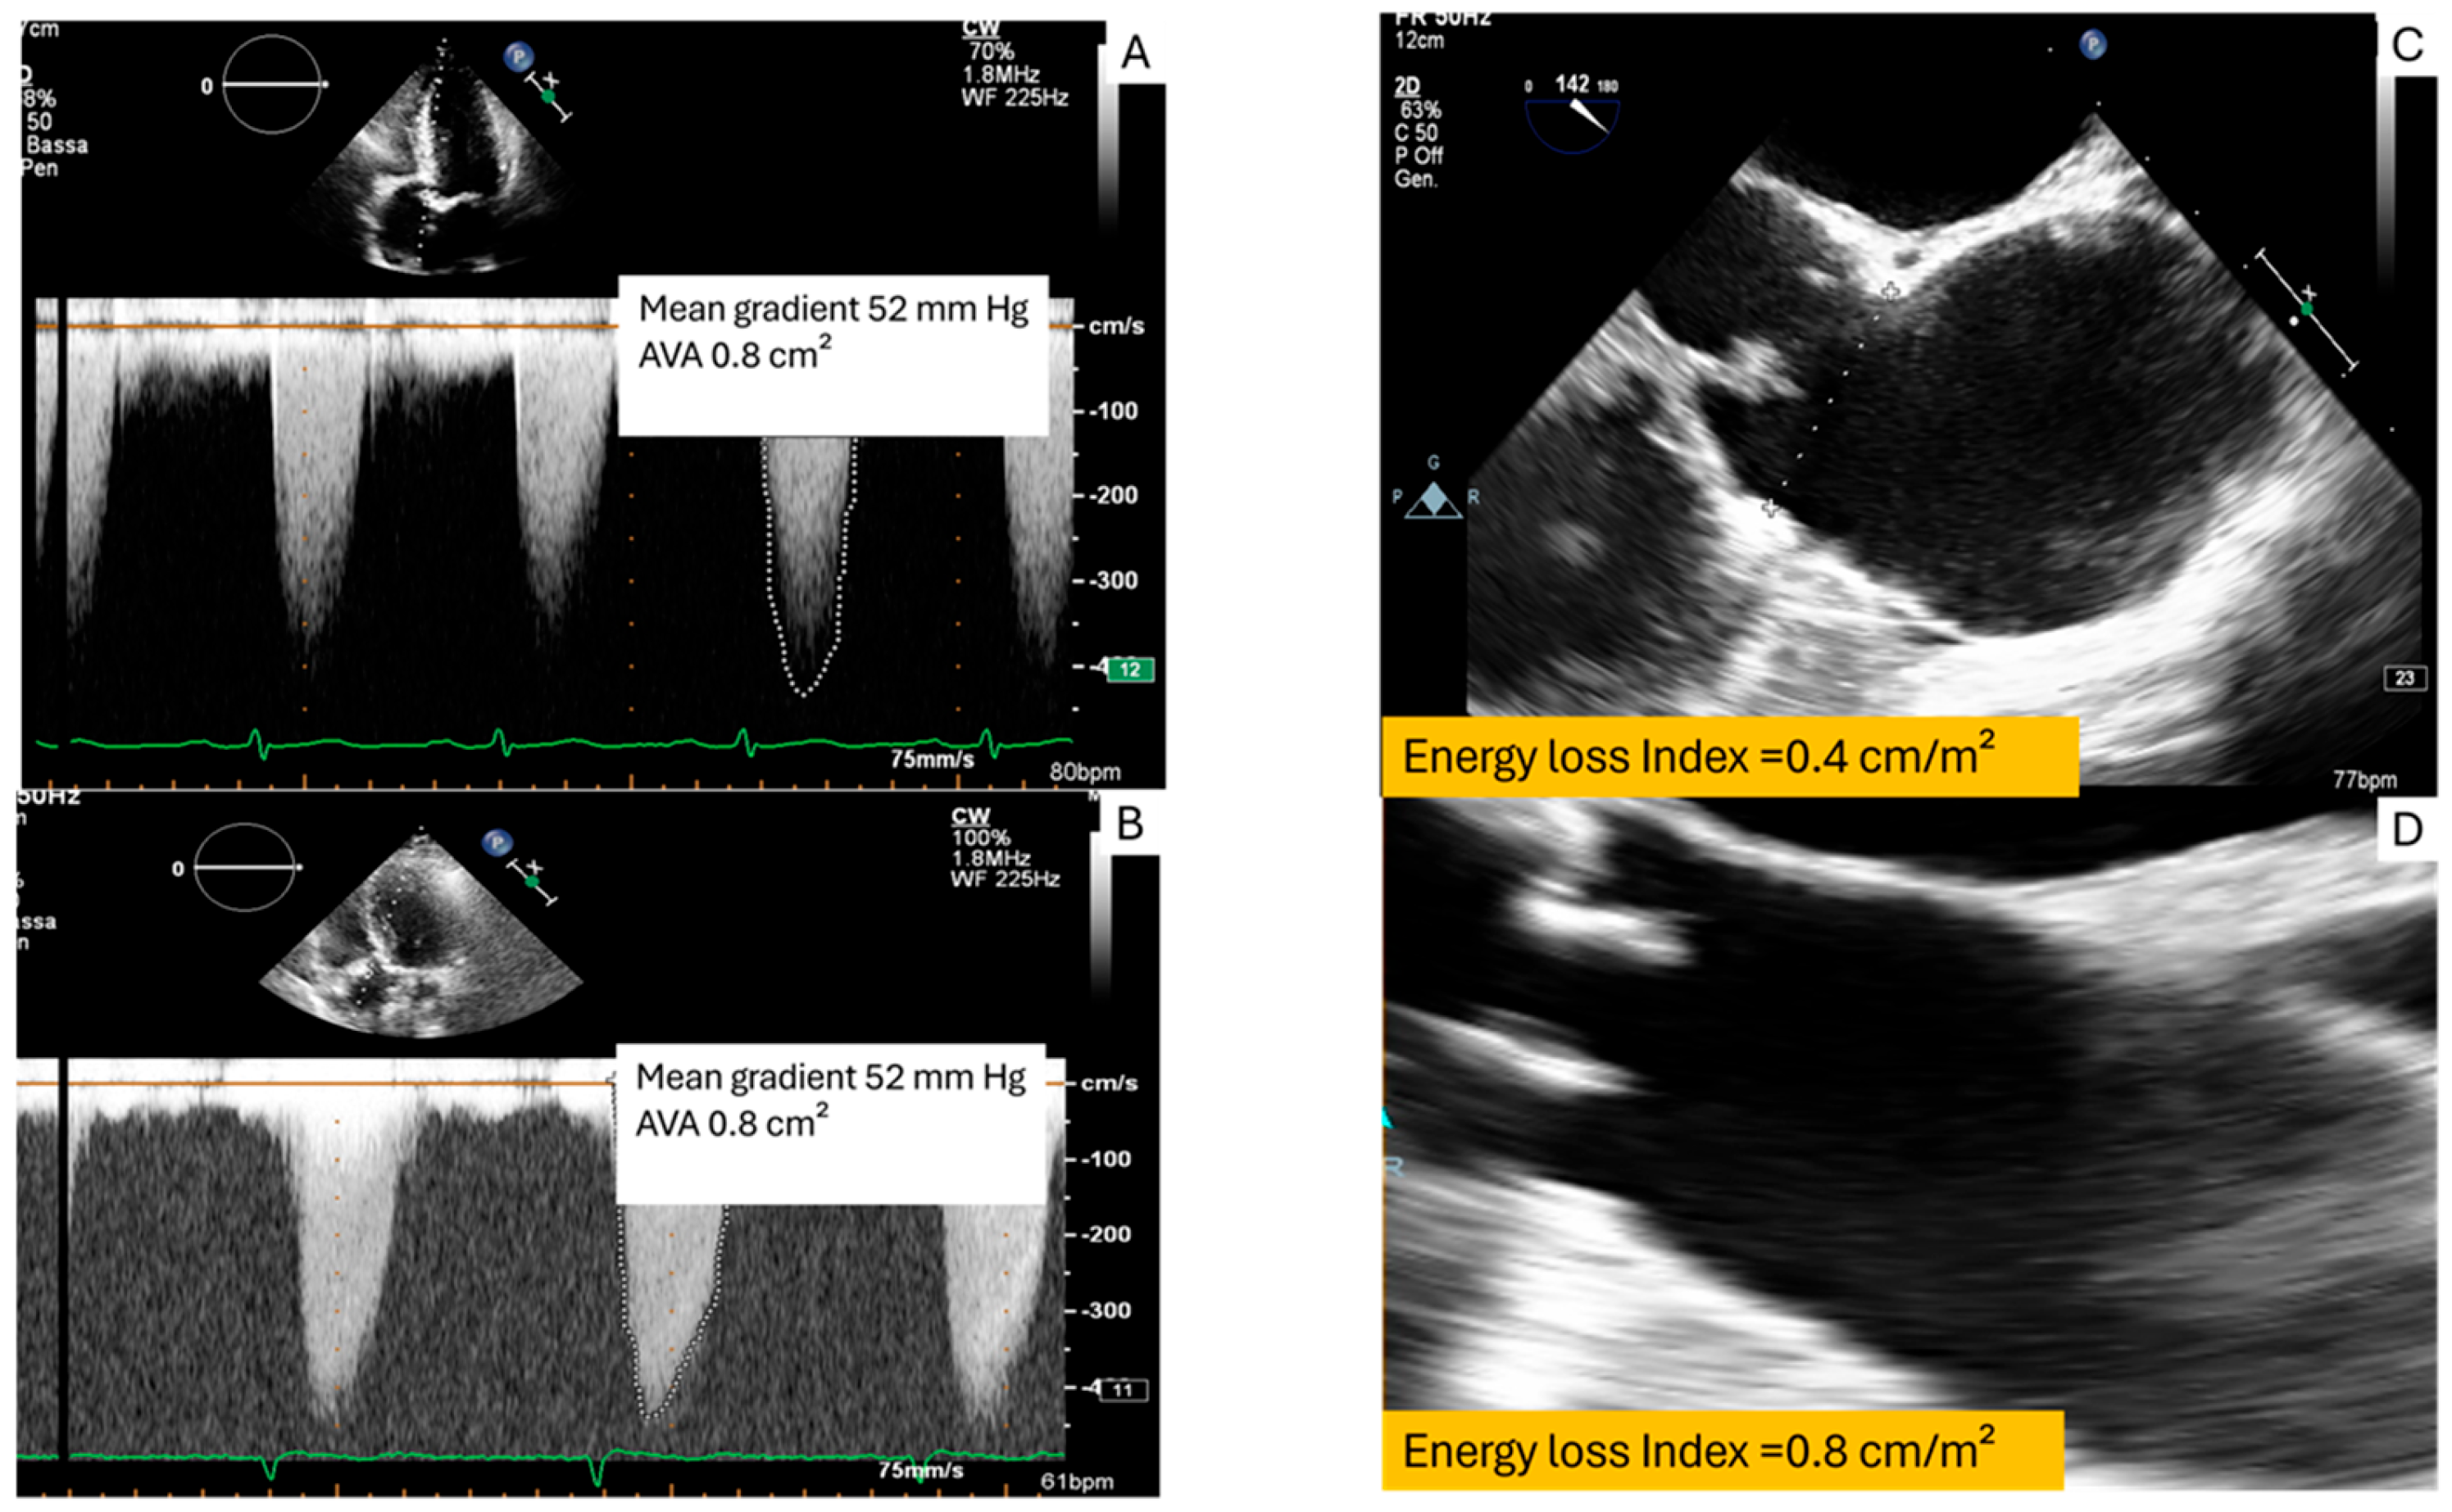

2.1. Transvalvular Aortic Gradient and Pressure Recovery